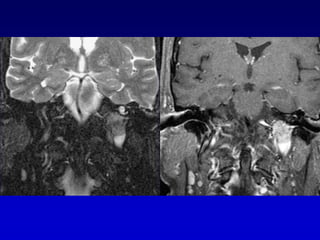

DWIFLAIR

Lesión intracanalicularScreening con  T2 DRIVEExclusión con secuencias T1 Gd que son las secuencias mas sensibles para el Schwannoma intracanalicular, pero no siempre especificas, a veces es difícil la diferenciación con neuritis

Secuencias T2 (DRIVE)Secuencias T2 muy finas permiten información esencial y por lo tanto,  se usan de rutina . Ellas permiten la evaluación de  Tamaño del tumorErosión osea del CAI Neuritis vs ( nervio normal)  Schwannoma

Secuencias T2 (DRIVE)Con el T2 puede verse el LCR en el fondo de saco del CAI